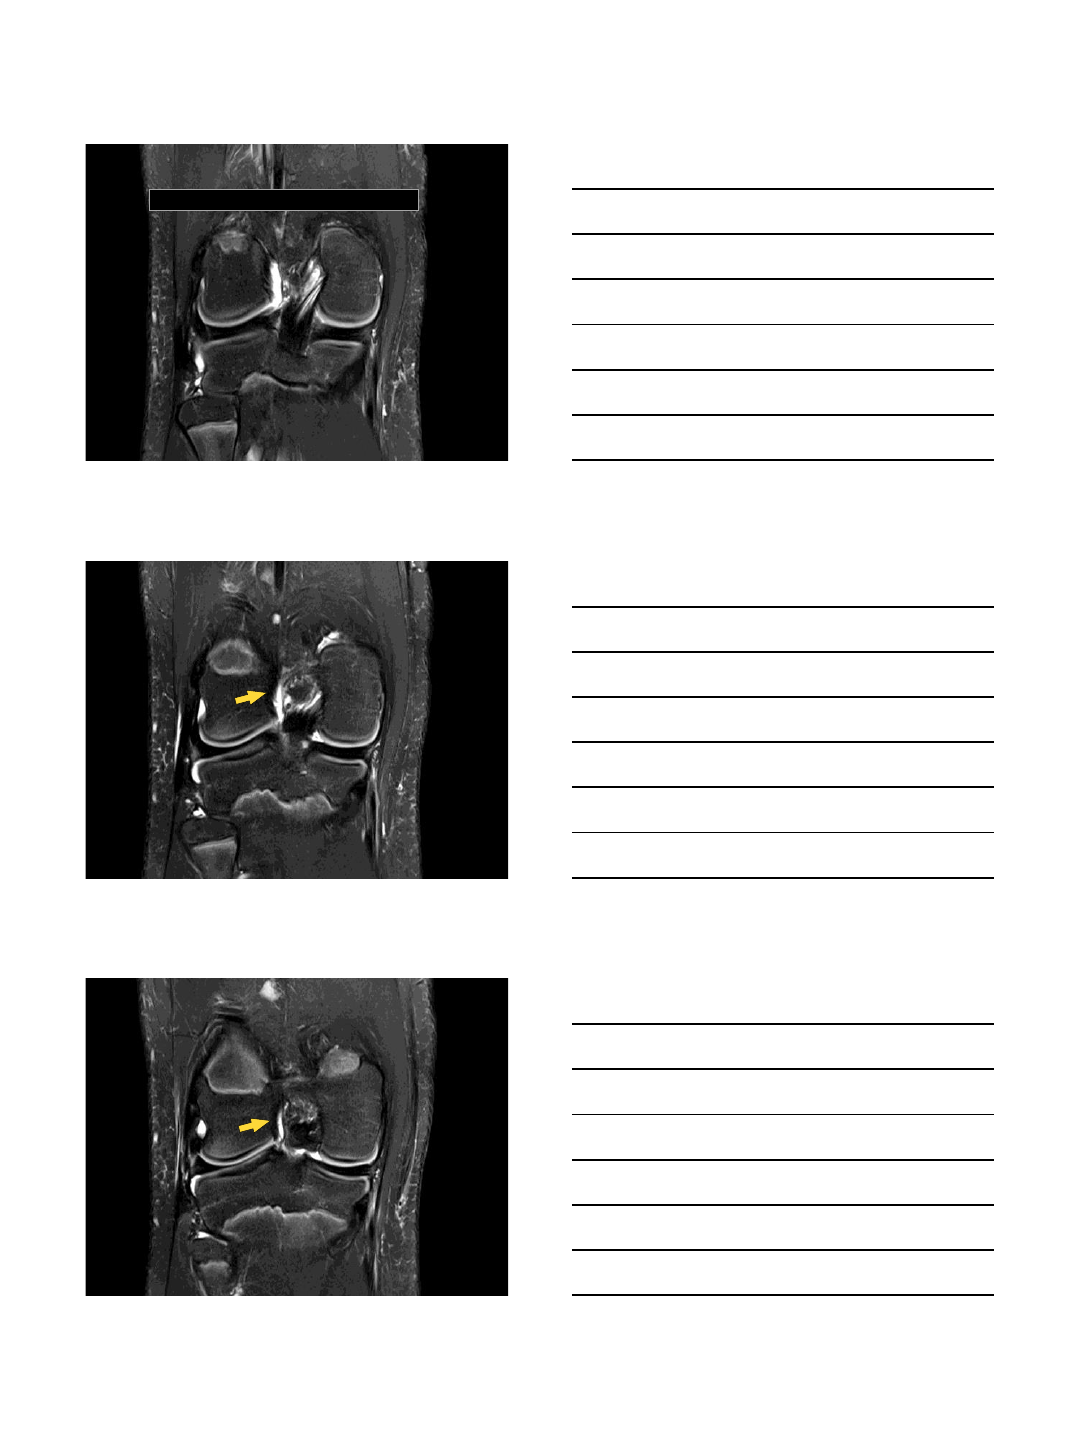

Coronal

10/13/2015

AM

PL

Different patient:

ACL may blend with anterior

horn lateral meniscus